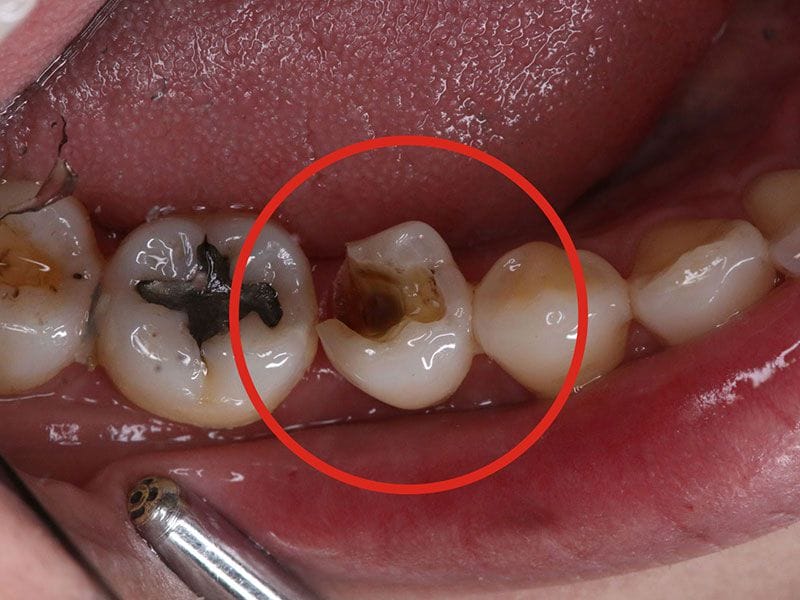

除汞前